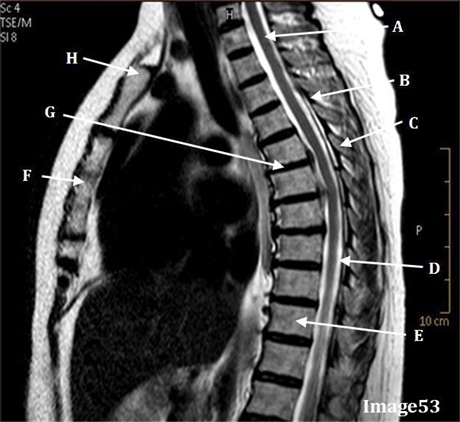

Image 53 is an example of:

T2 Sag thoracic spine